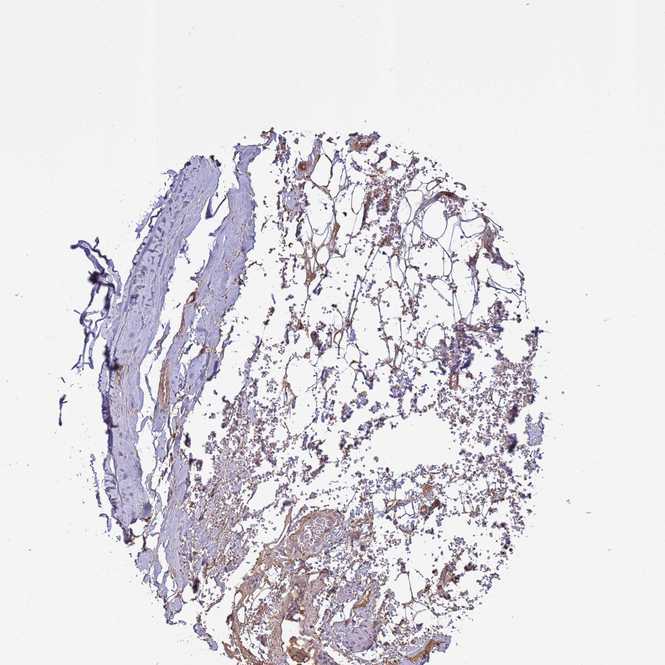

ADIPOSE TISSUE - Antibody stainingi

Antibody staining in the annotated cell types in the current human tissue is reported as not detected, low, medium, or high, based on conventional immunohistochemistry profiling in selected tissues. This score is based on the combination of the staining intensity and fraction of stained cells.

Each image is clickable and will lead to virtual microscopy that enables deeper exploration of all samples and also displays staining intensity scores, fraction scores and subcellular localization as well as patient and tissue information for each sample.

Antibody HPA017963

Adipocytes Low